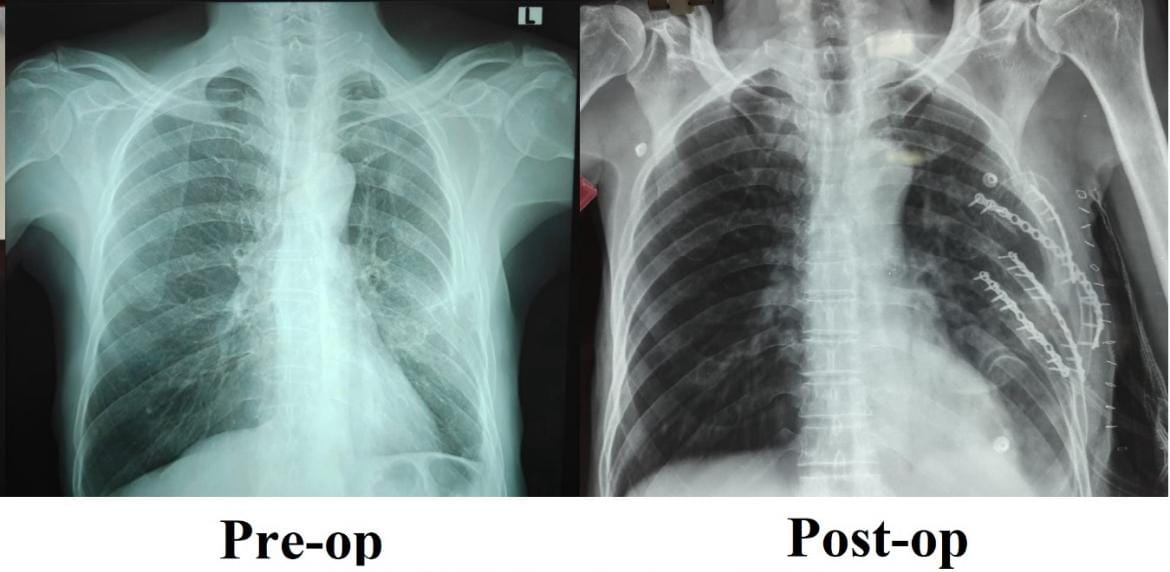

எஸ்ஆர்எம் மருத்துவக் கல்லூரி மருத்துவமனை மற்றும் ஆராய்ச்சி மையத்தின் ஒரு அங்கமாக இயங்கும் விபத்துக் காயங்களுக்கான அறுவைசிகிச்சை குழு, இம்மருத்துவமனையில் முதன் முறையாக தனது ‘விலா எலும்பு நிலைநிறுத்தல்‘ அறுவைசிகிச்சையை வெற்றிகரமாக நிகழ்த்தி ஒரு புதிய சாதனை படைத்திருக்கிறது. விபத்து காயங்களுக்கு மேம்பட்ட, நவீன சிகிச்சை அளித்து குணமாக்குவதில் இம்மையத்தின் திறனுக்கு சான்றாக இது திகழ்கிறது.

சாலை விபத்து ஒன்றில் சிக்கிய நோயாளி ஒருவருக்கு விலா எலும்புகள் பல இடங்களில் உடைந்திருந்தன. ஒரு மாதத்திற்கும் மேலாக முறையான வலி நிவாரண சிகிச்சைகளும், இயன்முறை சிகிச்சைகளும் அளிக்கப்பட்ட போதிலும், அவர் தொடர்ந்து கடுமையான நெஞ்சு வலியால் அவதிப்பட்டார். எலும்புகள் சரியாக இணையாததாலும், முறிந்த விலா எலும்புகளின் நிலையற்ற தன்மையாலும், ஆழமாக சுவாசிப்பதில் சிரமம், சரியாக தூங்க இயலாமை மற்றும் அன்றாடப் பணிகளைச் செய்ய முடியாத நிலை அவருக்கு நீடித்தது.

நிலைமையின் தீவிரத்தை உணர்ந்த பொது அறுவை சிகிச்சைத் துறையின் இணைப் பேராசிரியர் டாக்டர் விஜயன் P தலைமையிலான குழுவினர், முறிவுகள் ஏற்பட்டிருந்த விலா எலும்புகளை மீண்டும் சீரமைத்து நிலைநிறுத்தும் சிறப்பு அறுவை சிகிச்சையை இவருக்குமேற்கொண்டனர்.

அறுவை சிகிச்சையைத் தொடர்ந்து, இந்நோயாளி வலி குறைந்து, இயல்பாக சுவாசிக்கத் தொடங்கினார். மிக விரைவாகக் குணமடைந்த அவரால் மீண்டும் தன்னம்பிக்கையோடு இயல்பான பணிகளுக்கு இப்போது திரும்புவது சாத்தியமாகியிருக்கிறது.